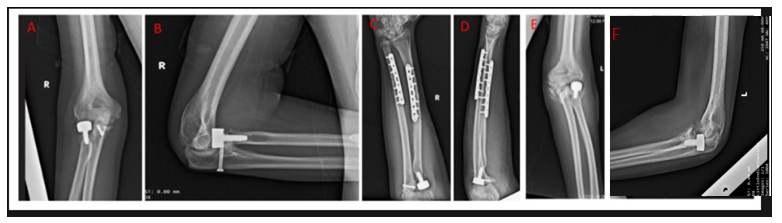

A muscle-strengthening program was started in the 4th month to strengthen the stabilization role of periarticular muscles [6]. At the 6-month follow-up, a clinical and radiological assessment (Figs. 5 and 6) was done, and the patient showed steady improvement in ROM in both elbows, demonstrating significant progress compared to pre-operative status. On radiological assessment, no elbow instability was seen, assessed by the radiocapitellar line made by passing through the middle of the radius shaft passing through the capitellum on lateral elbow radiographs in any degree of elbow flexion.

Figure 5: Post-operative follow up (at 6 months) X-rays of right elbow (a) anteroposterior and (b) lateral view, right forearm (c) anteroposterior and (d) lateral view, and left elbow (e) anteroposterior and (f) lateral view.